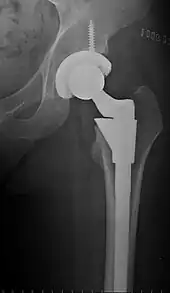

The prosthetic implant used in hip replacement consists of three parts: the acetabular cup, the femoral component, and the articular interface. Options exist for different people and indications. The evidence for a number of newer devices is not very good, including: ceramic-on-ceramic bearings, modular femoral necks, and uncemented monoblock cups.[74] Correct selection of the prosthesis is important.

Acetabular cup

The acetabular cup is the component which is placed into the acetabulum (hip socket). Cartilage and bone are removed from the acetabulum and the acetabular cup is attached using friction or cement. Some acetabular cups are one piece, while others are modular. One-piece (monobloc) shells are either ultra-high-molecular-weight polyethylene (UHMWPE) or metal, they have their articular surface machined on the inside surface of the cup and do not rely on a locking mechanism to hold a liner in place. A monobloc polyethylene cup is cemented in place while a metal cup is held in place by a metal coating on the outside of the cup. Modular cups consist of two pieces, a shell and liner. The shell is made of metal; the outside has a porous coating while the inside contains a locking mechanism designed to accept a liner. Two types of porous coating used to form a friction fit are sintered beads and a foam metal design to mimic the trabeculae of cancellous bone and initial stability is influenced by under-reaming and insertion force.[75] Permanent fixation is achieved as bone grows onto or into the porous coating. Screws can be used to lag the shell to the bone providing even more fixation. Polyethylene liners are placed into the shell and connected by a rim locking mechanism; ceramic and metal liners are attached with a Morse taper.

Femoral component

The femoral component is the component that fits in the femur (thigh bone). Bone is removed and the femur is shaped to accept the femoral stem with attached prosthetic femoral head (ball). There are two types of fixation: cemented and uncemented. Cemented stems use acrylic bone cement to form a mantle between the stem and to the bone. Uncemented stems use friction, shape and surface coatings to stimulate bone to remodel and bond to the implant. Stems are made of multiple materials (titanium, cobalt chromium, stainless steel, and polymer composites) and they can be monolithic or modular. Modular components consist of different head dimensions and/or modular neck orientations; these attach via a taper similar to a Morse taper. These options allow for variability in leg length, offset and version. Femoral heads are made of metal or ceramic material. Metal heads, made of cobalt chromium for hardness, are machined to size and then polished to reduce wear of the socket liner. Ceramic heads are more smooth than polished metal heads, have a lower coefficient of friction than a cobalt chrome head, and in theory will wear down the socket liner more slowly. As of early 2011, follow-up studies in patients have not demonstrated significant reductions in wear rates between the various types of femoral heads on the market. Ceramic implants are more brittle and may break after being implanted.

Configuration

Post-operative projectional radiography is routinely performed to ensure proper configuration of hip prostheses.

The direction of the acetabular cup influences the range of motion of the leg, and also affects the risk of dislocation.[7] For this purpose, the acetabular inclination and the acetabular anteversion are measurements of cup angulation in the coronal plane and the sagittal plane, respectively.